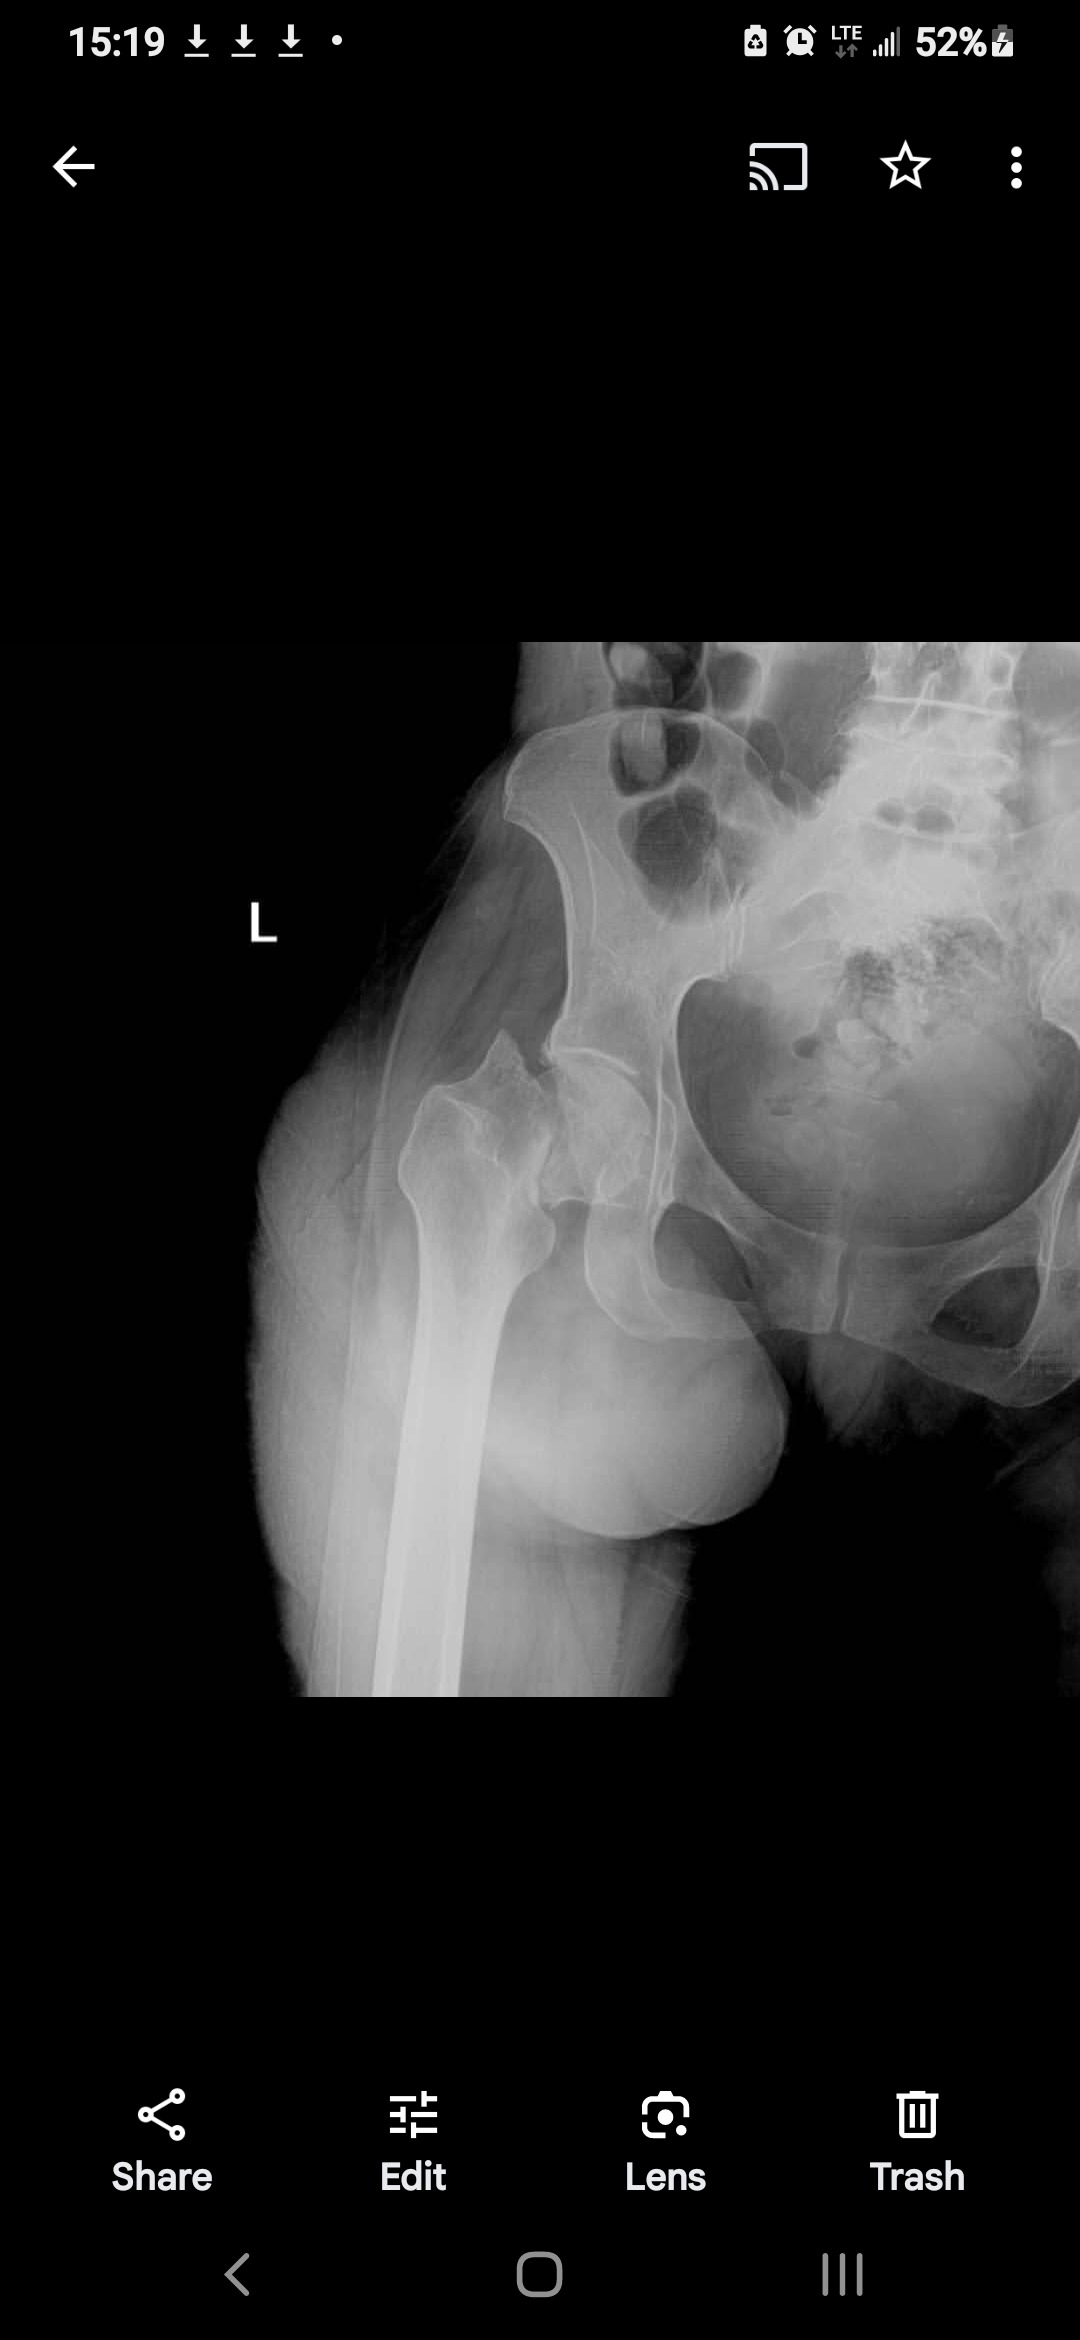

However, in an attempt to speed up my recovery, I slipped and fell, fracturing my hip. Due to financial constraints, I couldn't receive immediate medical attention. Six months later, I'm still in pain, unable to work,walk, and struggling to care for my children.

Fortunately, Orthopedic Surgeon has agreed to perform the hip replacement surgery. *The only thing needed now is the implant, which costs $1500usd*.The Orthopedic Surgeon has kindly offered to take care of the rest.